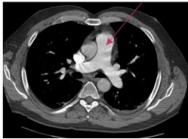

7) What is the most appropriate imaging modality for staging lung cancer?

19) Radio-anatomie du thorax, choisissez l’un des suivants:

27) Radio-anatomie du thorax, choisissez l’un des suivants:

34) Radio-anatomie du thorax, choisissez l’un des suivants: